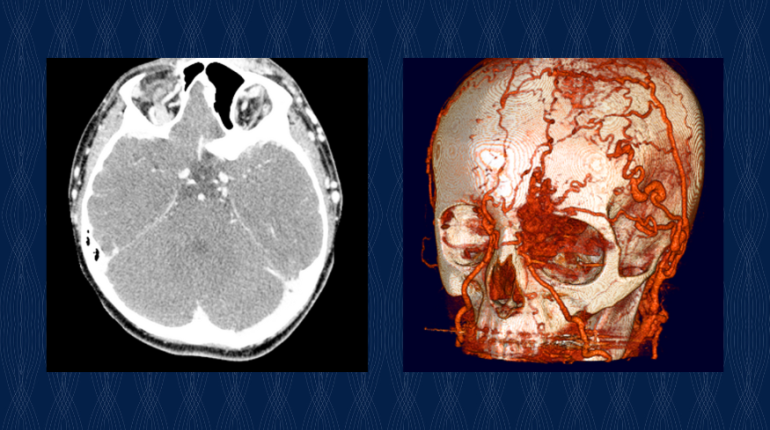

It was around that time that I finally discovered medical imaging while looking for references for my art. Medical art is about depicting what can’t be seen, but with diagnostic and interventional imaging, you can literally peer directly into the body. So I was actually using CT scans and MRI and ultrasound as references for my art. That’s how I got the radiology bug! I went back and did my residency in radiology, and then a fellowship in pediatric radiology.

Radiology is all about visualizing the structure and function of the human body. It’s about seeing anatomy, seeing diseases, seeing complex relationships, and seeing change over time. Diagnostic imaging is the vision of health care.

Interventional radiology. I want to give this institution an awesome interventional radiology department. When most people think of imaging, they’re thinking of diagnostic imaging — X-rays, CT scans, ultrasound, MRI — the ability to see disease, to diagnose it accurately. Interventional radiology is the ability to do image-guided therapy. To put catheters or wires or coils or balloons into the body to treat disease. And unlike open surgery, where you have these big scars, it’s typically done with a tiny incision that’s only about 2 or 3 millimeters. And you can treat everything from aneurysms to abscesses to cancers. It’s extraordinary.